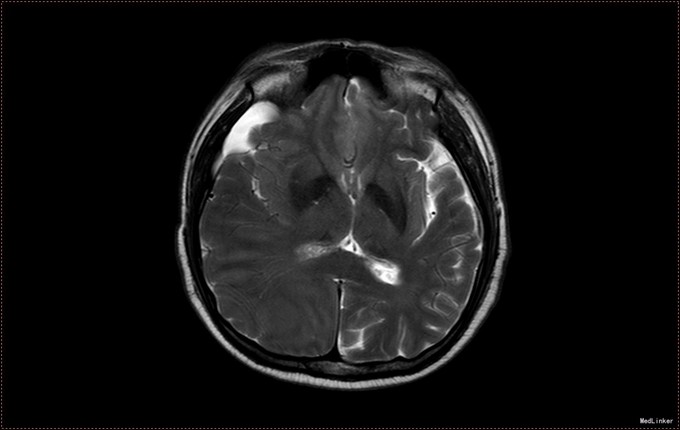

患者,男,53岁。以“左侧肢体疼痛伴无力1周”为主诉入院。患者1周前无明显诱因出现左侧肢体无力,伴酸痛,头部闷胀感,症状持续不缓解,于我院就诊,行头部CT及MR提示右侧顶枕叶硬膜下血肿。右侧额颞叶蛛网膜囊肿。患者为求进一步治疗,急诊以“硬膜下血肿”为诊断,收入病房。患者病来精神状态差,饮食睡眠可,二便可,体重无明显变化。否认近期头部外伤史。

入院查体:T:36.5℃ ,P:68次/分 ,BP:130/80mmHg , R:16次/分。步入病房,自主体位。神清语明,问答准确,查体合作,精神状态良好,定向力完整。粗测视野正常,双侧瞳孔等大正圆,D≈3.0mm,双侧眼球活动自如,对光反射灵敏。四肢活动自如,左侧肢体肌力V-级,右侧肢体肌力Ⅴ级,肌张力正常。深浅感觉检查未见异常。头CT及MR提示右侧颞极蛛网膜囊肿,右侧亚急性硬膜下血肿

患者诊断明确,完善术前检查行局麻右侧钻孔冲洗引流术,予常规治疗。术后3天拔管,复查头CT硬膜下血肿消失,但脑组织膨胀不良。患者左侧肢体肌力恢复正常,无头晕头沉症状,顺利出院。